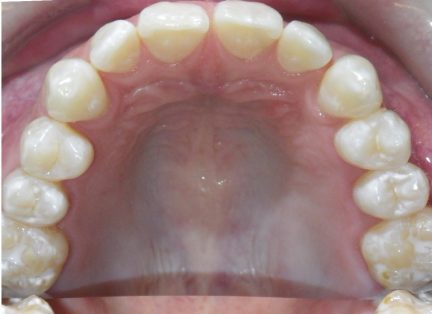

État initial

Classe I, Classe III, articulé croisé antérieur, surplomb augmenté, béance, espacement

Égression, inclinaison, réduction interproximale, élastiques : Classe III